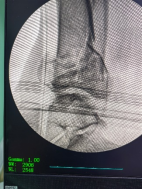

透視檢查骨折端